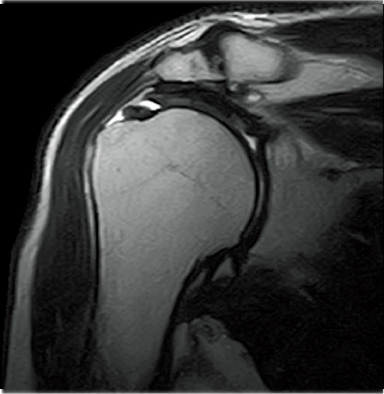

T2WI

FatSep-T2*WI

FatSep-T2WI